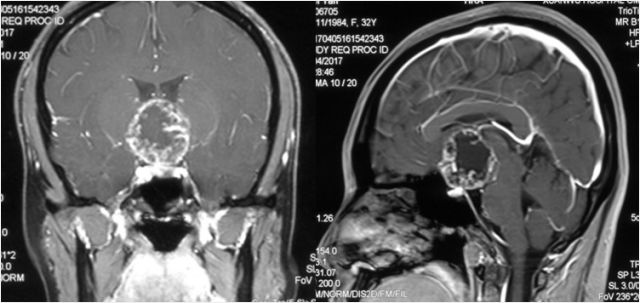

听神经瘤

手术体位个性化选择

术前

术后